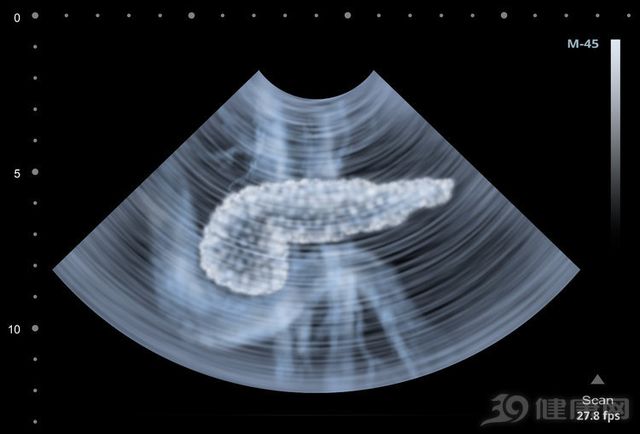

28/05/2020 16:13Bác sĩ có 27 năm kinh nghiệm điều trị ung thư lại tử vong vì ung thư tuyến tụy: Vì sao vị bác sĩ này không phát hiện mình bị bệnh?

Vào tháng 3/2018, Vương Lỗi, phó Giám đốc Bệnh viện liên kết thứ 6 thuộc Đại học Trung Sơn, người đã dành cả cuộc đời của mình để điều trị ung thư đại trực tràng cho người bệnh, lại được chẩn đoán mắc bệnh ung thư tuyến tụy giai đoạn cuối ở tuổi 49. Khi kết quả xét nghiệm này xuất hiện, bác sĩ Vương Lỗi vẫn đang giúp bệnh nhân thực hiện phẫu thuật trên bàn mổ. Đối mặt với căn bệnh ung thư, ông thú nhận: "Cảm giác bất lực đang lan rộng".

Ngay từ nửa cuối năm 2017, bác sĩ Vương Lỗi đã thường cảm thấy đau thắt lưng, bị cảm lạnh và sốt thời gian dài vẫn chưa chữa khỏi, nhưng vì ông quá bận với công việc, còn thực hiện rất nhiều cuộc phẫu thuật quan trọng cho bệnh nhân, nên ông không thể dành thời gian cho bản thân. Do đó, khối u tuyến tụy đã trở thành ung thư giai đoạn cuối.

1. Vị trí của tuyến tụy rất bí mật, các triệu chứng không rõ ràng, giai đoạn sớm rất khó phát hiện

Ngay cả chuyên gia điều trị bệnh ung thư như bác sĩ Vương Lỗi cũng không phát hiện ra rằng sự khó chịu của bản thân có liên đến ung thư tuyến tụy. Điều này là do ung thư tuyến tụy nằm sâu trong bụng, phía sau ruột và các cơ quan nội tạng không nhạy cảm với đau như bề mặt cơ thể, vì vậy ung thư tuyến tụy giai đoạn sớm hầu như không có triệu chứng và không dễ phát hiện.

Khi bệnh nhân có các triệu chứng phổ biến của ung thư tuyến tụy như đau bụng, vàng da và giảm cân, ung thư tuyến tụy đã phát triển đến giai đoạn giữa và cuối, hiệu quả điều trị rất kém. Ví dụ, bác sĩ Vương Lỗi sau khi được chẩn đoán đã nói về tình trạng bệnh của bản thân: "Nếu không được điều trị, khoảng 1-2 tháng có thể tử vong, ngay cả khi được điều trị tích cực, cũng chỉ có thể kéo dài sự sống trong hai hoặc ba năm".